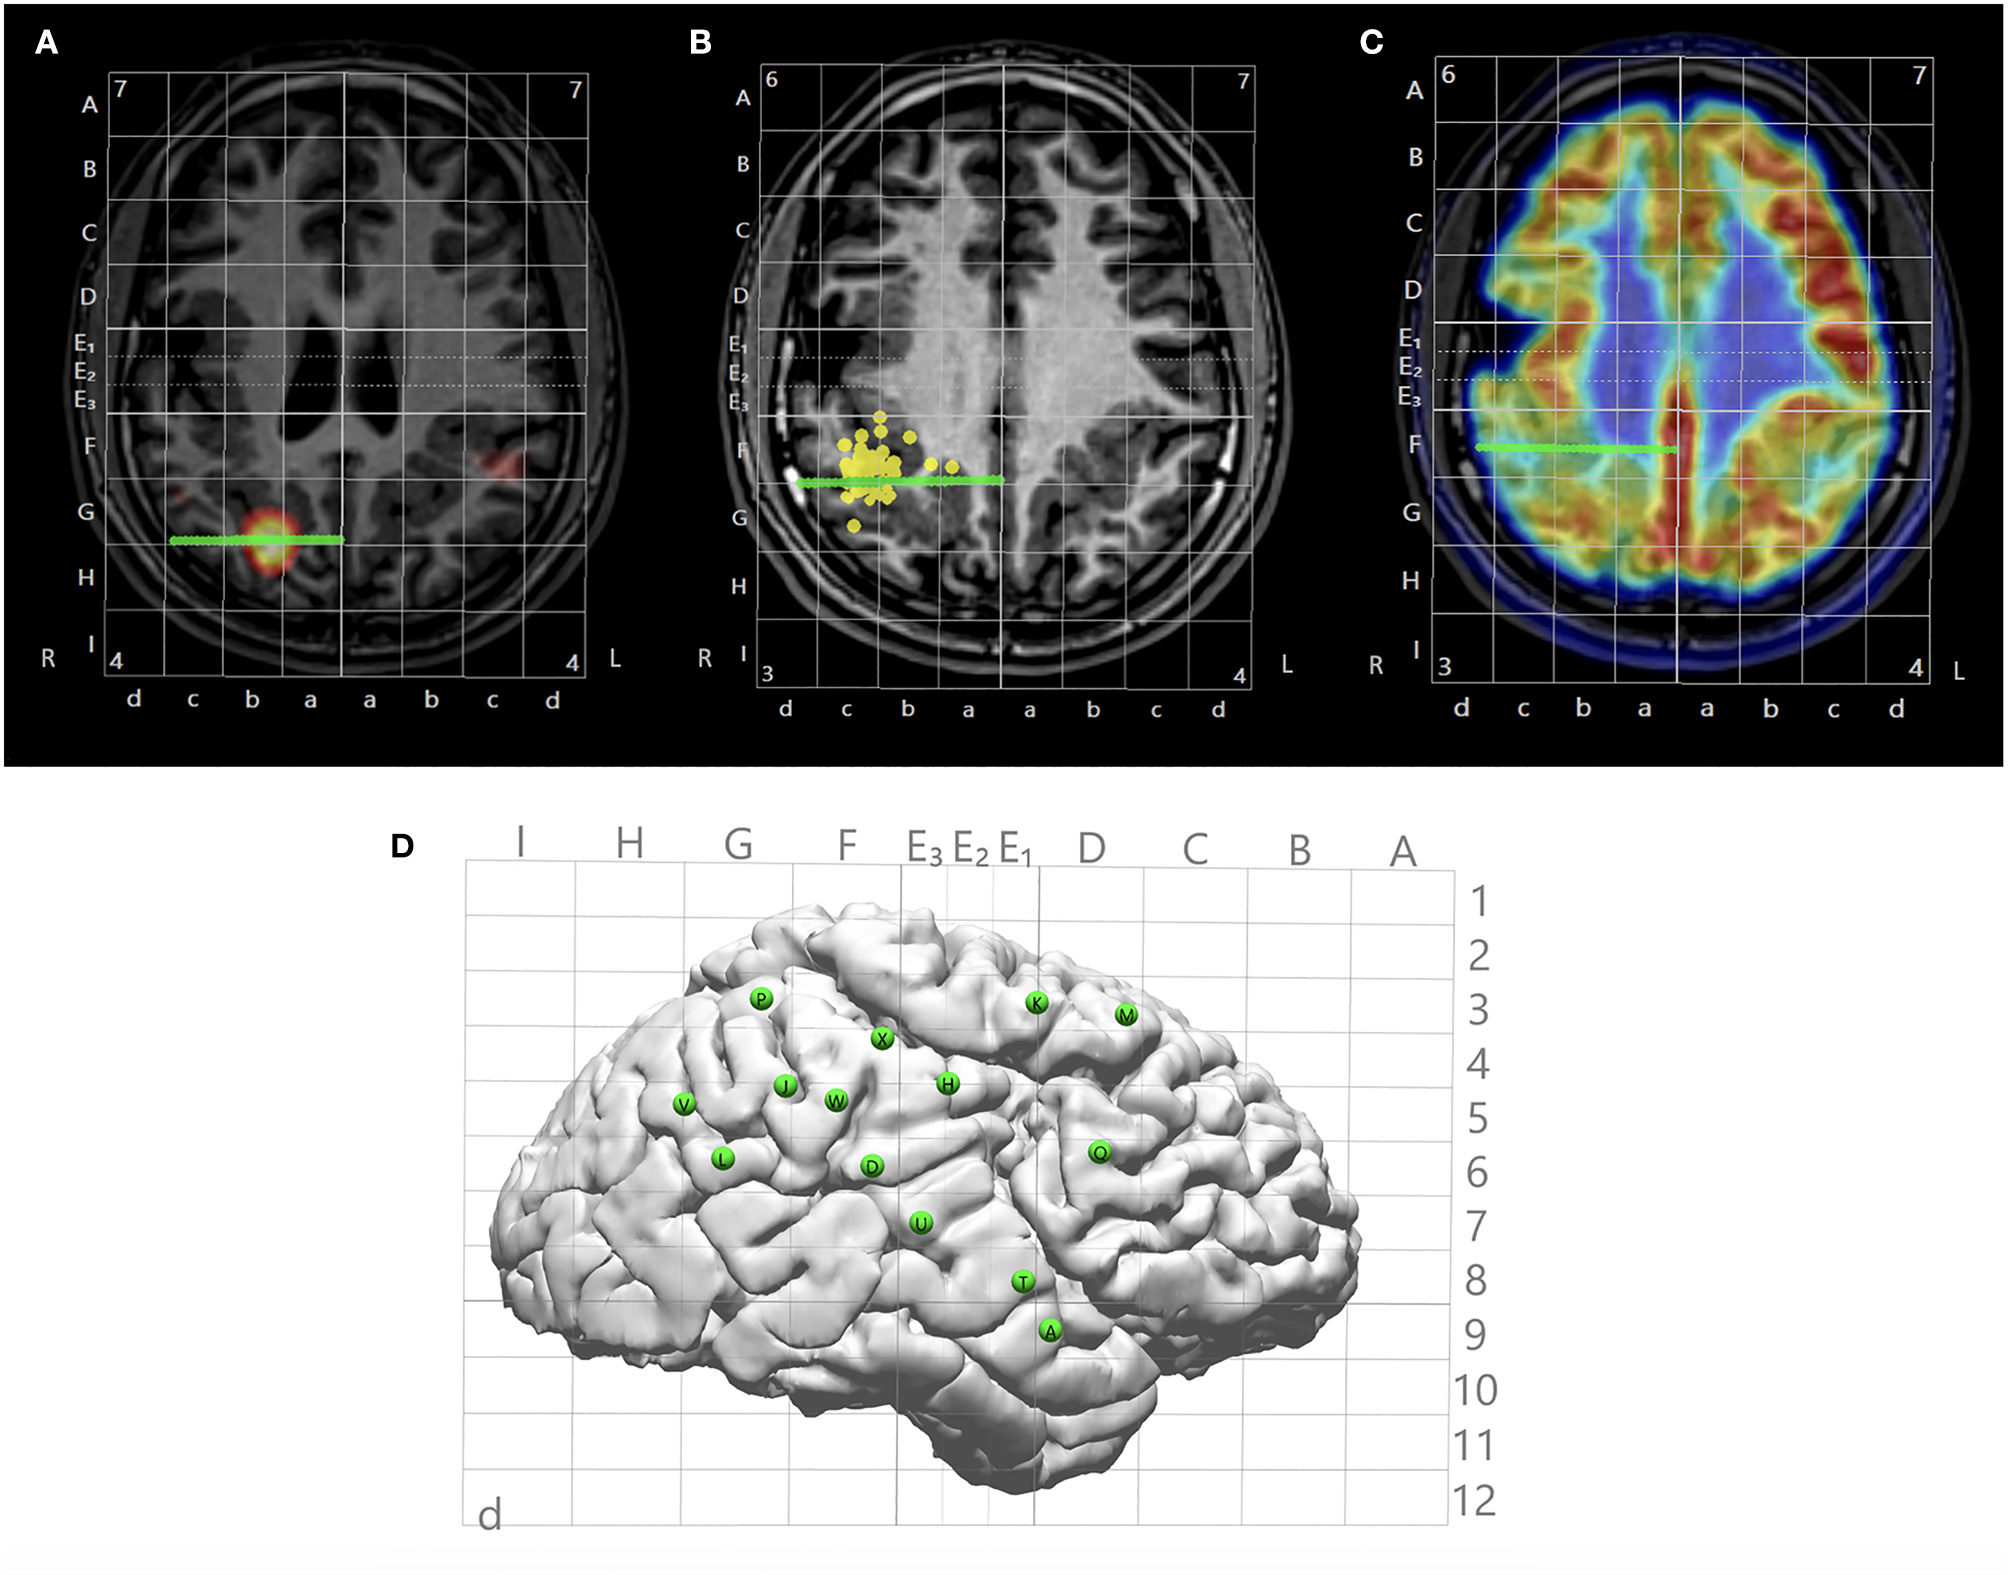

Figure 3

Illustration of multimodal integration assisting trajectory planning. (A) A trajectory planned to target a hyperperfusion region shown by subtraction ictal SPECT co-registered with MRI (SISCOM) analysis. (B) A trajectory planned to target a tight MEG cluster. (C) A trajectory planned to target hypometabolic regions on the PET. (D) Entry points of all planned trajectories shown on the cortical surface with Talairach grid overlaid.

SEEG Trajectory Planning

After all images from the non-invasive modalities were fused and Talairach coordinates defined, trajectories of SEEG could be planned based on any chosen modality that had localization value to the case (Figures 3A–C). An entry point and a target point were defined for each electrode, and the trajectories were created as a straight line connecting these two points (as shown in Figures 2, 3), avoiding major vasculatures (shown by the CTA or MRA) especially at the entry point. The Talairach grid can be used as a reference for the definition of the entry and target points. All planned trajectories can then be displayed on the cortical surface to examine their coverage (Figure 3D), and can be exported as high-intensity lines on the T1-weighed base image volume as DICOM images, which can be further incorporated into the neuronavigation systems, e.g., ROSA (Medtech, Montpellier, France) and Brainlab (Brainlab, Feldkirchen, Germany), to facilitate implantation in the OR.